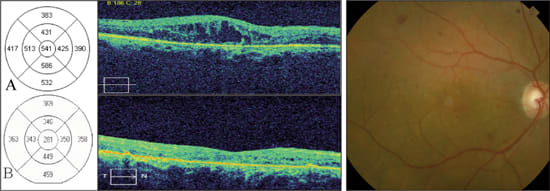

Figure 3. Sequential SD-OCT images from an 82-year-old female with diabetic macular edema in the right eye. Color fundus photograph shows exudates with macular thickening.

A: Horizontal scans through the fovea show distortion of the normal foveal contour with a large central intraretinal cyst. The retinal map shows a central foveal thickness of 841 μm. Best-corrected visual acuity was 20/400.

B: One month after intravitreal triamcinolone acetonide, SD-OCT reveals marked improvement of foveal thickness (113 μm) and resolution of cystoid macular edema. Best-corrected visual acuity remained 20/400.

An 82-year-old female with insulin dependent diabetes mellitus was evaluated for proliferative diabetic retinopathy (PDR) and diabetic macular edema in both eyes. Her other medical problems reported in the history included hypertension and chronic obstructive pulmonary disease. Her ophthalmic history included a combined pars plana vitrectomy with cataract surgery two years earlier. Best corrected visual acuity in the right eye was 20/400 and SD-OCT showed CME with a central foveal thickness of 841 microns (Figure 3A).

The right eye was treated with intravitreal triamcinolone acetonide (40 mg/ml). One month later, her vision remained 20/400 although the patient noted subjective improvement. SD-OCT measured central foveal thickness improved to 113 microns and there was restoration of the foveal contour (Figure 3B).